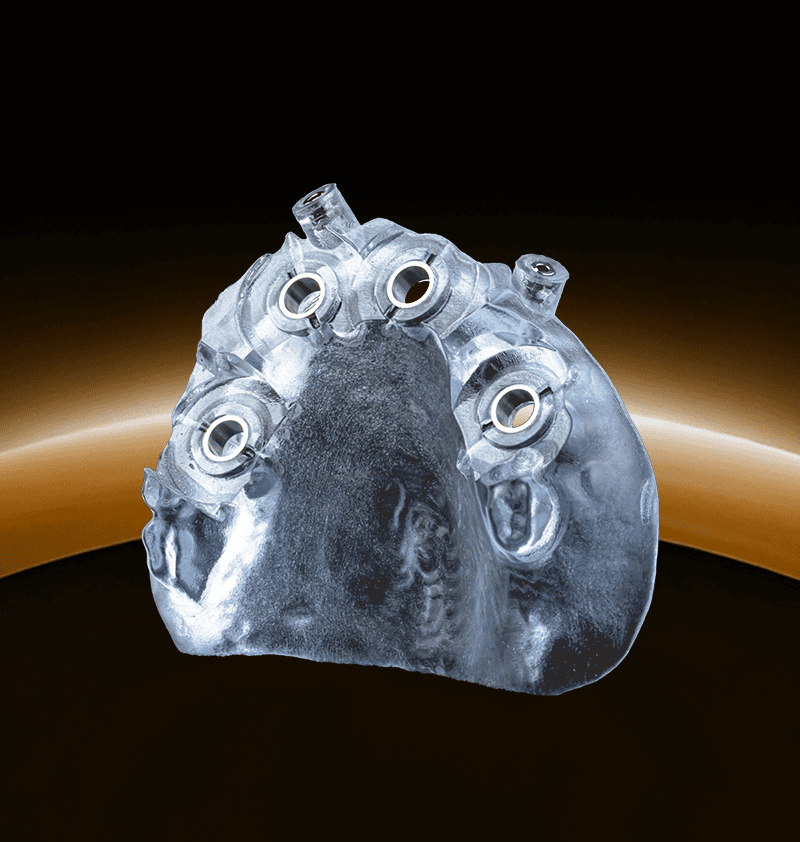

Seamless digital solutions for every step of the implant journey.

From scan to final delivery, 3Sixty streamlines your workflow with smart planning, precision guides, and real clinical support.

3Sixty is a digital dental lab with 150+ dental and technical experts supporting every case. From treatment planning to surgical guides and full-arch workflows like our groundbreaking Anatomic Guide®, we help streamline complex procedures. Trusted by over 3,000 dentists, we make digital implant dentistry simpler, faster, and more predictable.